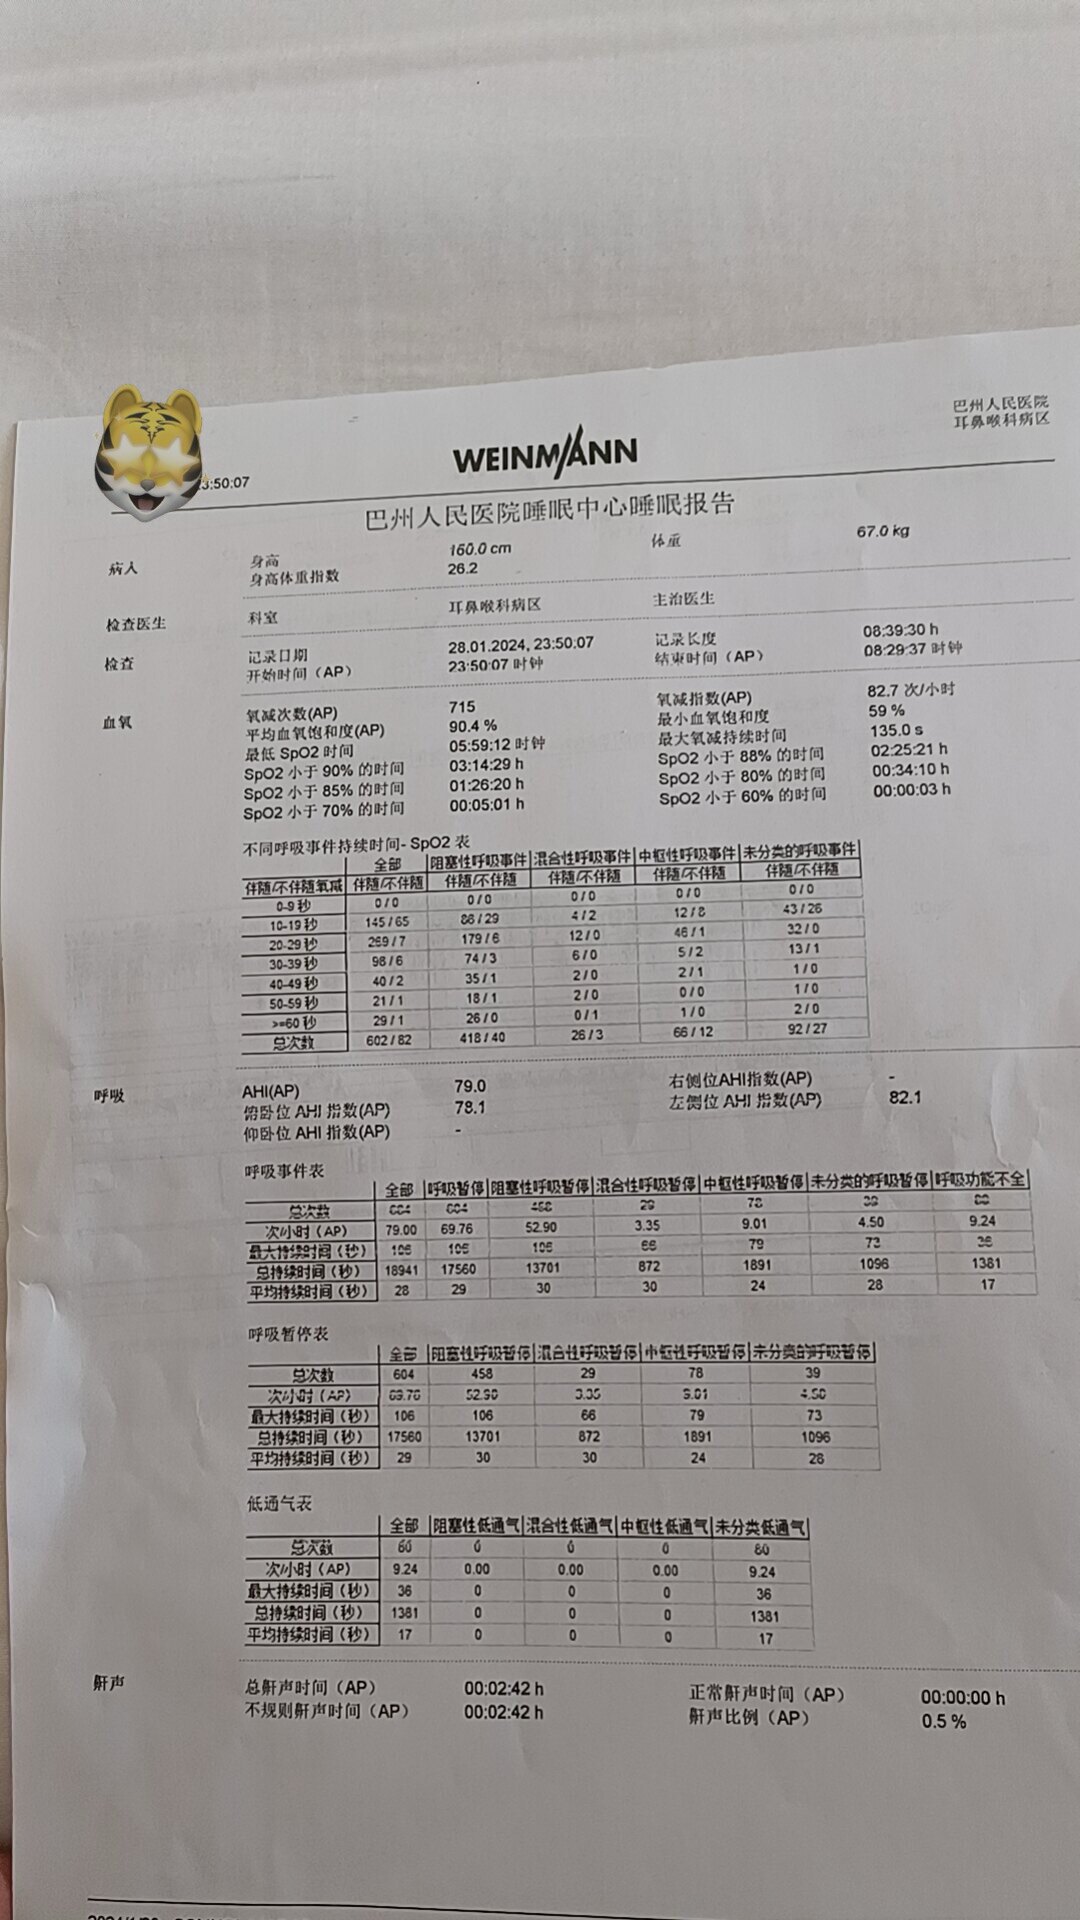

之前同一天做过“鼾症兄弟”、“鼾症兄妹”和“鼾症父女”,这是第一次给“鼾症母女”同一天手术。这对母女来自新疆巴音郭楞,重度鼾症父亲37岁,因为扁桃体肥大,自小打鼾,4年前产后打鼾加重,伴夜间憋醒,严重影响睡眠,当地医生建议患者戴呼吸机,但是她无法耐受呼吸机。电话咨询后,下定决心来广州找我手术。同时她也把4岁女儿打鼾和张口呼吸的情况也详细告诉我,鼾症女儿因为扁桃体3度肥大,腺样体堵塞后鼻孔2/3,造成张口呼吸,对于这样的孩子,一定需要早点手术干预,不然会影响面部发育和生长发育,甚至智力发育。所以我就让她们母女一起来广州找我手术。手术时发现母女俩的扁桃体肥大,因为女孩子4岁,我常规保留双下极扁桃体的1/5和腺样体的1/5。希望母女手术后身体早日恢复正常!有一个安稳的睡眠质量,健健康康的生活!